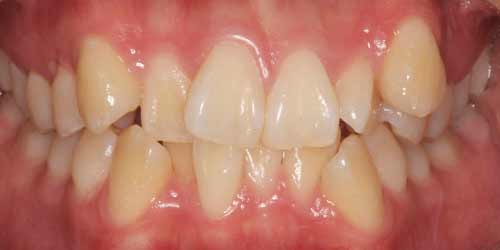

نامرتبی دندانها ( Crowding )

شایع ترین ناهنجاری ارتودنسی که اکثر بیماران را ترغیب به انجام درمان ارتودنسی می کند نامرتبی دندانها می باشد.

عوارض نامرتبی دندانها :

1. بهم خوردن زیبایی لبخند و کاهش اعتماد به نفس در بسیاری از افراد به هنگام لبخند زدن

2. سختتر شدن رعایت بهداشت به دلیل عدم دسترسی مسواک به سطوح دندان های نامرتب و امکان ایجاد پوسیدگی و بیماری لثه